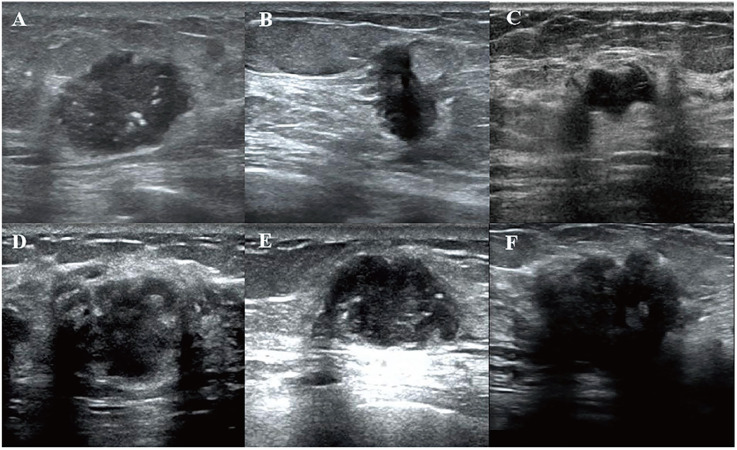

IntroductionTumor-infiltrating lymphocytes (TILs) are key indicators of immune response and prognosis in breast cancer (BC). Accurate prediction of TIL levels is essential for guiding personalized treatment strategies. This study aimed to develop and evaluate machine learning models using ultrasound-derived radiomics and clinical features to predict TIL levels in BC.MethodsThis retrospective study included 256 BC patients between January 2019 and August 2023, who were randomly divided into training (n = 179) and test (n = 77) cohorts. Radiomics features were extracted from the intratumor and peritumor regions in ultrasound images. Feature selection was performed using the "Boruta" package in R to iteratively remove non-significant features. Extra Trees Classifier was used to construct radiomics and clinical models. A combined radiomics-clinical (R-C) model was also developed. Model performance was evaluated using the area under the receiver operating characteristic curve (AUC), accuracy, sensitivity, specificity, and decision curve analysis (DCA) to assess clinical utility. A nomogram was created based on the best-performing model.ResultsA total of 1712 radiomics features were extracted from the intratumor and peritumor regions. The Boruta method selected five key features (four from the peritumor and one from the intratumor) for model construction. Clinical features, including immunohistochemistry, tumor size, shape, and echo characteristics, showed significant differences between high (≥10%) and low (<10%) TIL groups. Both the R-C and radiomics models outperformed the clinical model in the test cohort (area under the curve values of 0.869/0.838 vs 0.627, P < .05). Calibration curves and Brier scores demonstrated superior accuracy and calibration for the R-C and radiomics models. DCA revealed the highest net benefit of the R-C model at intermediate threshold probabilities.ConclusionUltrasound-derived radiomics effectively predicts TIL levels in BC, providing valuable insights for personalized treatment and surveillance strategies.

Abstract Image